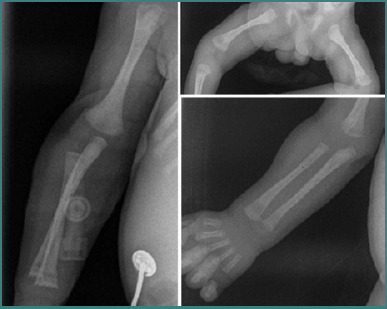

Congenital syphilis is one of the most well-known congenital infections. Despite notable progress in early diagnosis of syphilis paired with the accessibility of cost-effective treatment and preventive strategies, a few cases continue to be diagnosed in the department of obstetrics. This paper presents a case study of an infant with low birth weight, delivered by an adolescent mother, part of a marginalized demographic group. Due to the mother's lack of routine prenatal care, the infant's management required a series of investigations to establish a comprehensive differential diagnosis. Maternal serological assessments for syphilis, including both non-treponemal antibody test (RPR) and treponemal antibody test (TPHA), yielded positive results following fetal extraction via cesarean section, specifically after diagnosis of syphilis in the infant. Within the first 24 hours of life, newborn serologic tests for syphilis (STS) (including RPR and TPHA assays) exhibited reactivity with titers equivalent to maternal samples. Furthermore, at three weeks of life, the neonatal STS titer exceeded that of the maternal titer, displaying a fourfold increase over the maternal STS level. This finding was concomitant with the detection of IgM antibodies against T. pallidum. Screening for other congenital infections yielded negative results. Subsequent to the high-risk infant follow-up, in accordance with the National Guidelines, the infant had a good outcome.